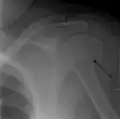

A fracture of the greater tuberosity as seen on AP X ray -

A fracture of the greater tuberosity of the humerus -